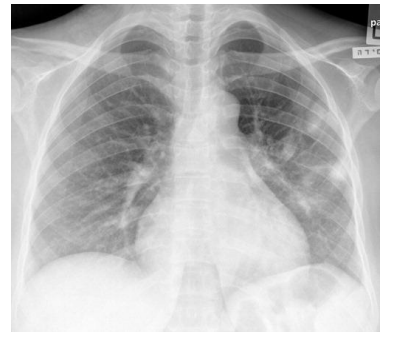

Escolar de 7 anos, acompanhado no ambulatório, foi levado à emergência por dispneia. Mãe relatou que filho estava há

2 dias com mialgia, febre e coriza, evoluindo nas últimas 12 horas com piora da febre e dispneia progressiva. Ao exame,

estava febril (39ºC), taquidispneico, PA no percentil 90 e com SpO2 = 88% em ar ambiente. Realizada radiografia de

tórax (abaixo). O resultado de RT-PCR foi positivo para influenza A e negativo para Covid-19. Os exames laboratoriais

mostraram leucocitose com linfopenia, PCR elevada, e pró-calcitonina baixa.

Diante do caso, qual a principal suspeita diagnóstica e a conduta adequada?

Diante do caso, qual a principal suspeita diagnóstica e a conduta adequada?